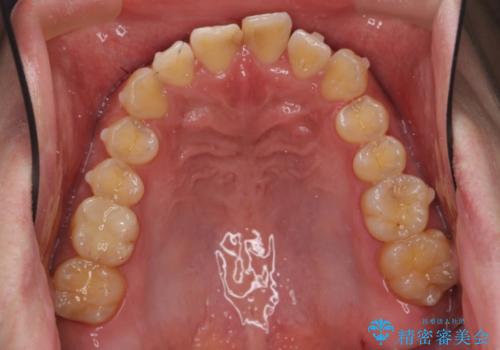

前歯のねじれを 1年かけずに矯正 インビザライン

- 前歯のねじれを主訴に来院。

インビザラインで治療しました。

前歯のねじれをセラミックで治そうとすると、抜髄といって、神経の治療が必要になる上、歯の幅も制限が出て理想的にはなりません。

保定の必要がありますが、天然歯を並べる矯正治療では、治療後の心配事が非常に少なく、保存的な処置となります。